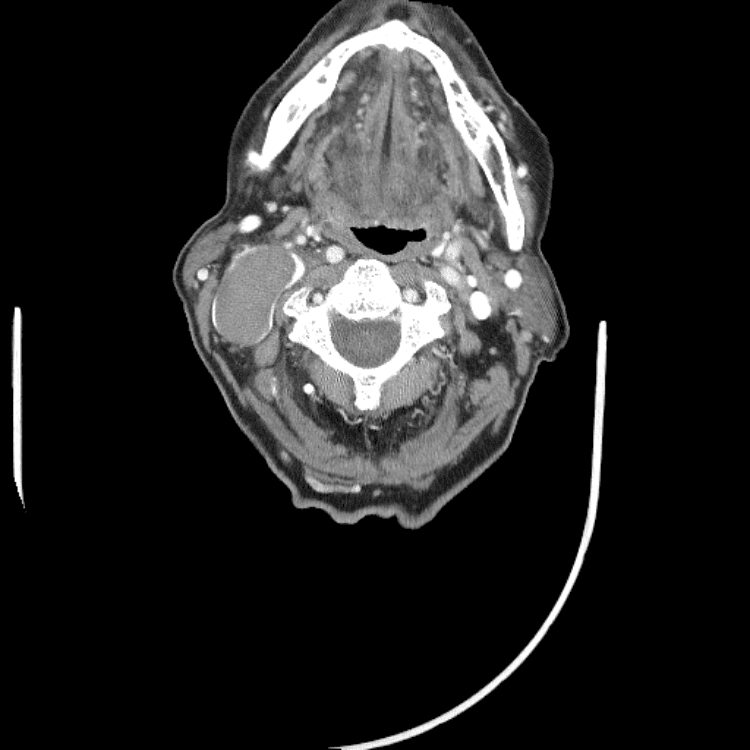

Head and Neck

Practice

Simulates call by including subtle or difficult cases and some normals.

27 cases